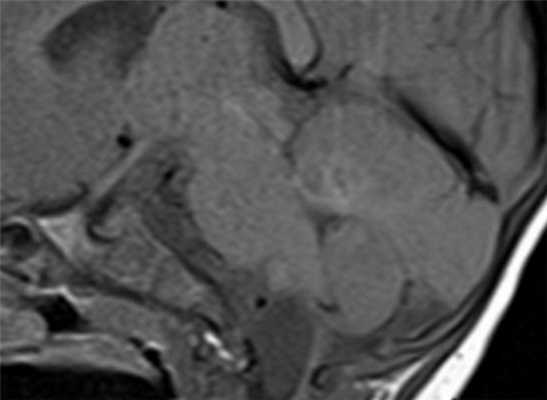

МРТ головного мозга. Т1-взвешенные корональная и сагиттальная МРТ. Эпидермоидная киста левой височной доли.